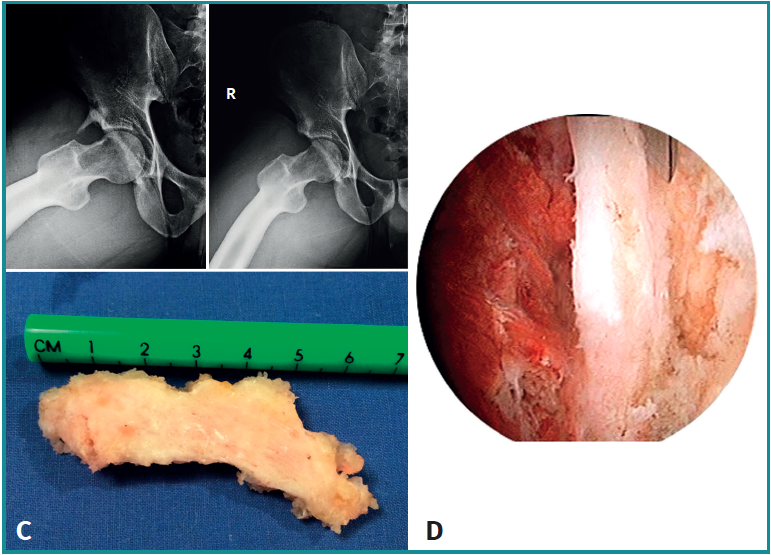

(A3) Fragmentos grandes con una línea vertical en el borde acetabular superior-lateral compatible con fracturas por estrés consolidadas o no consolidadas

- Características y morfología radiográfica: tamaño grande y línea de fractura perpendicular o vertical en relación con el techo acetabular (Figura 3).

- Localización y lesiones asociadas: generalmente, medio lateral o ligeramente posterior en relación con el acetábulo y también con morfologías de CFA asociadas.

- Tratamiento: dependiendo de la cobertura que quede tras la extirpación, se decidirá si enuclear el fragmento o fijarlo. La planificación preoperatoria es por tanto crucial para garantizar que la escisión de la fractura/fragmento no dé como resultado una cobertura insuficiente o una inestabilidad iatrogénica. La medición del ángulo centro borde lateral y anterior al nivel de la extirpación planificada puede dar una indicación de una cobertura insuficiente resultante si el fragmento contribuye a la estabilidad de la cadera. En estos casos, debe considerarse la fijación quirúrgica mediante fijación con tornillo canulado asistida por artroscopia a través de la unión fibrocartilaginosa(4). En casos de fragmentos grandes que contribuyan simultáneamente al pinzamiento y la estabilidad, se puede realizar resección parcial y fijación del remanente. La utilización de una sutura sobre el tornillo de fijación ayudará a realizar la fijación labral sin tener que usar un arpón o anclaje(4)(Figura 4).